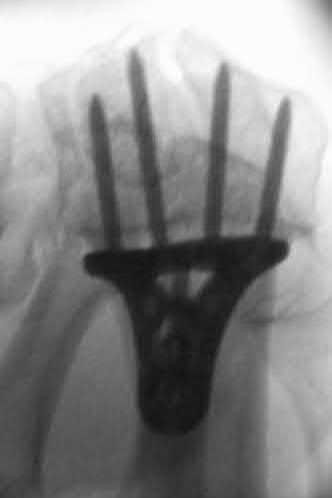

Question 9:

A 30-year-old male sustains a severe midfoot sprain. Radiographs reveal widening between the bases of the first and second metatarsals. The primary ligamentous stabilizer disrupted in this classic Lisfranc injury connects which two osseous structures?

Correct Answer: Medial cuneiform to 2nd metatarsal base

Explanation:

The Lisfranc ligament is the strongest ligament in the tarsometatarsal joint complex. It courses obliquely from the lateral aspect of the medial cuneiform to the medial base of the second metatarsal. It acts as the primary stabilizer of the second metatarsal base. Disruption results in the classic widening between the first and second rays, often with an avulsion fragment ('fleck sign').